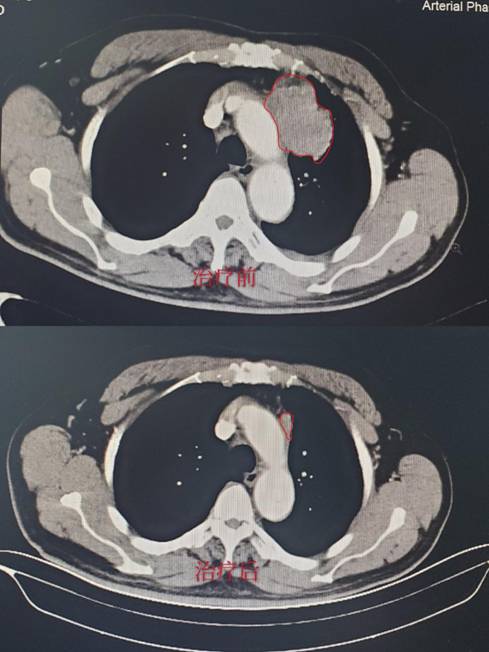

结直肠癌是我国高发疾病,晚期肠癌治疗需要靶向治疗联合化疗,靶向治疗费用昂贵。由上海复旦大学附属肿瘤医院及北京大学肿瘤医院牵头的转移性结直肠癌帕尼单抗生物类似药联合化疗的一项临床试验,我院也是参与单位之一,我院也给这类病人带来新希望。

经过严格筛选,目前有一例72岁高龄患者顺利进入临床试验,入院诊断:肠癌伴肝肺广泛转移,经过3周期治疗后肝肺病灶明显缩小达60%,且治疗无明显毒副作用,患者及家属对我们的治疗表示非常满意。(CT结果如下,红色线框内为肿瘤组织。)